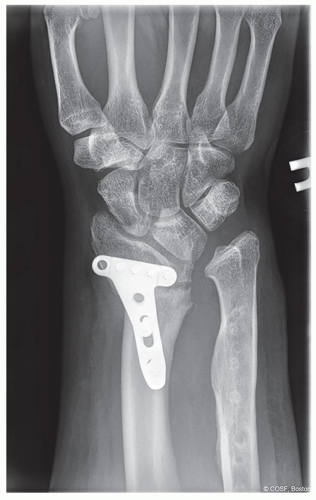

Lunate fossa deformity (Figure 15.1)

Volar and proximal carpal subluxation (Figure 15.2)

Distal radioulnar joint (DRUJ) incongruity secondary to distal radius deformity and ulna overgrowth (Figure 15.3)